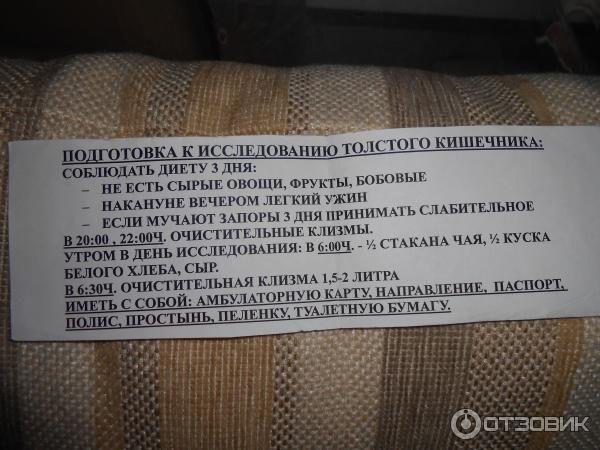

Подготовка к ирригоскопии: необходимые препараты